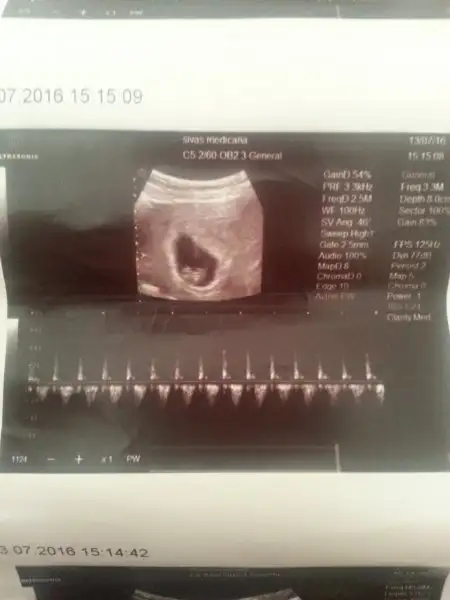

Evet arkadaslar Ramzi, Nub ve cin takvimi (öyleydi adi sanirim) kiz diyor benim bebise. Bakalim dogru cikacak mi yoksa tüm teorileri cökertecek miyim

Kızlar banada bakar mısınız ortada sanki ya

Eklentiler

• IMG_5090.webp

4,2 KB · Görüntüleme: 201